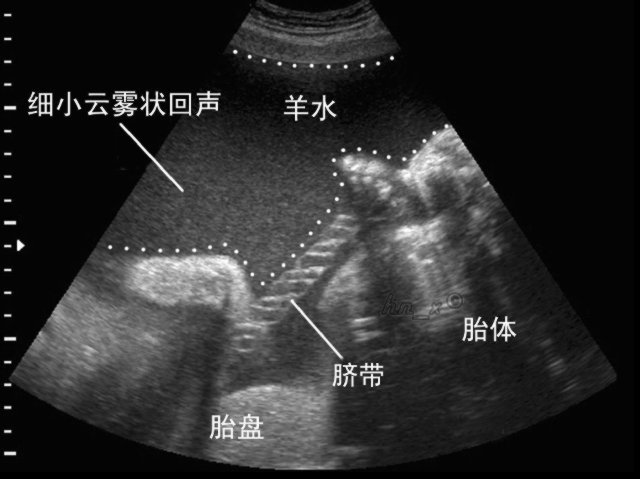

羊水深度是指,B超检查表示最大羊水池的垂直深度,小于2cm表示羊水过少,大于8cm表示羊水过多。 它为医学专业名词,是判断羊水多少的一个重要指标。羊水多,则胎儿可以健康成长;羊水少,就可以在胎儿临产期造成胎粪淤积,甚至早产或窒息。B超检查表示最大羊水池的垂直深度,羊水深度3-8cm为正常羊水量。小于3cm提示羊水过少,大于8cm提示羊水过多。

羊水指数:是将子宫分成左上,右上,左下和右下四个象限,四个象限的最大羊水暗区垂直深度之和为AFL,若AFL大于24cm诊断为羊水过多,若AFL在18-24cm之间时为可疑羊水过多或羊水偏多。

羊水测量:羊水量的测量,是评估怀孕正常与否的重要指标。但隔了一层肚皮,我们实在很难正确地去评估羊水的多少。

目前,医院大多是通过超音波来了解羊水量的状况,采取"羊水指数法"来确定羊水量是否正常。方法是:将子宫分为四个象限,分别量每个象限中羊水的最大深度,再相加求其总和。总和值在8~27厘米的范围之内属于正常状态,小于8为羊水过少,大于24则为羊水过多。